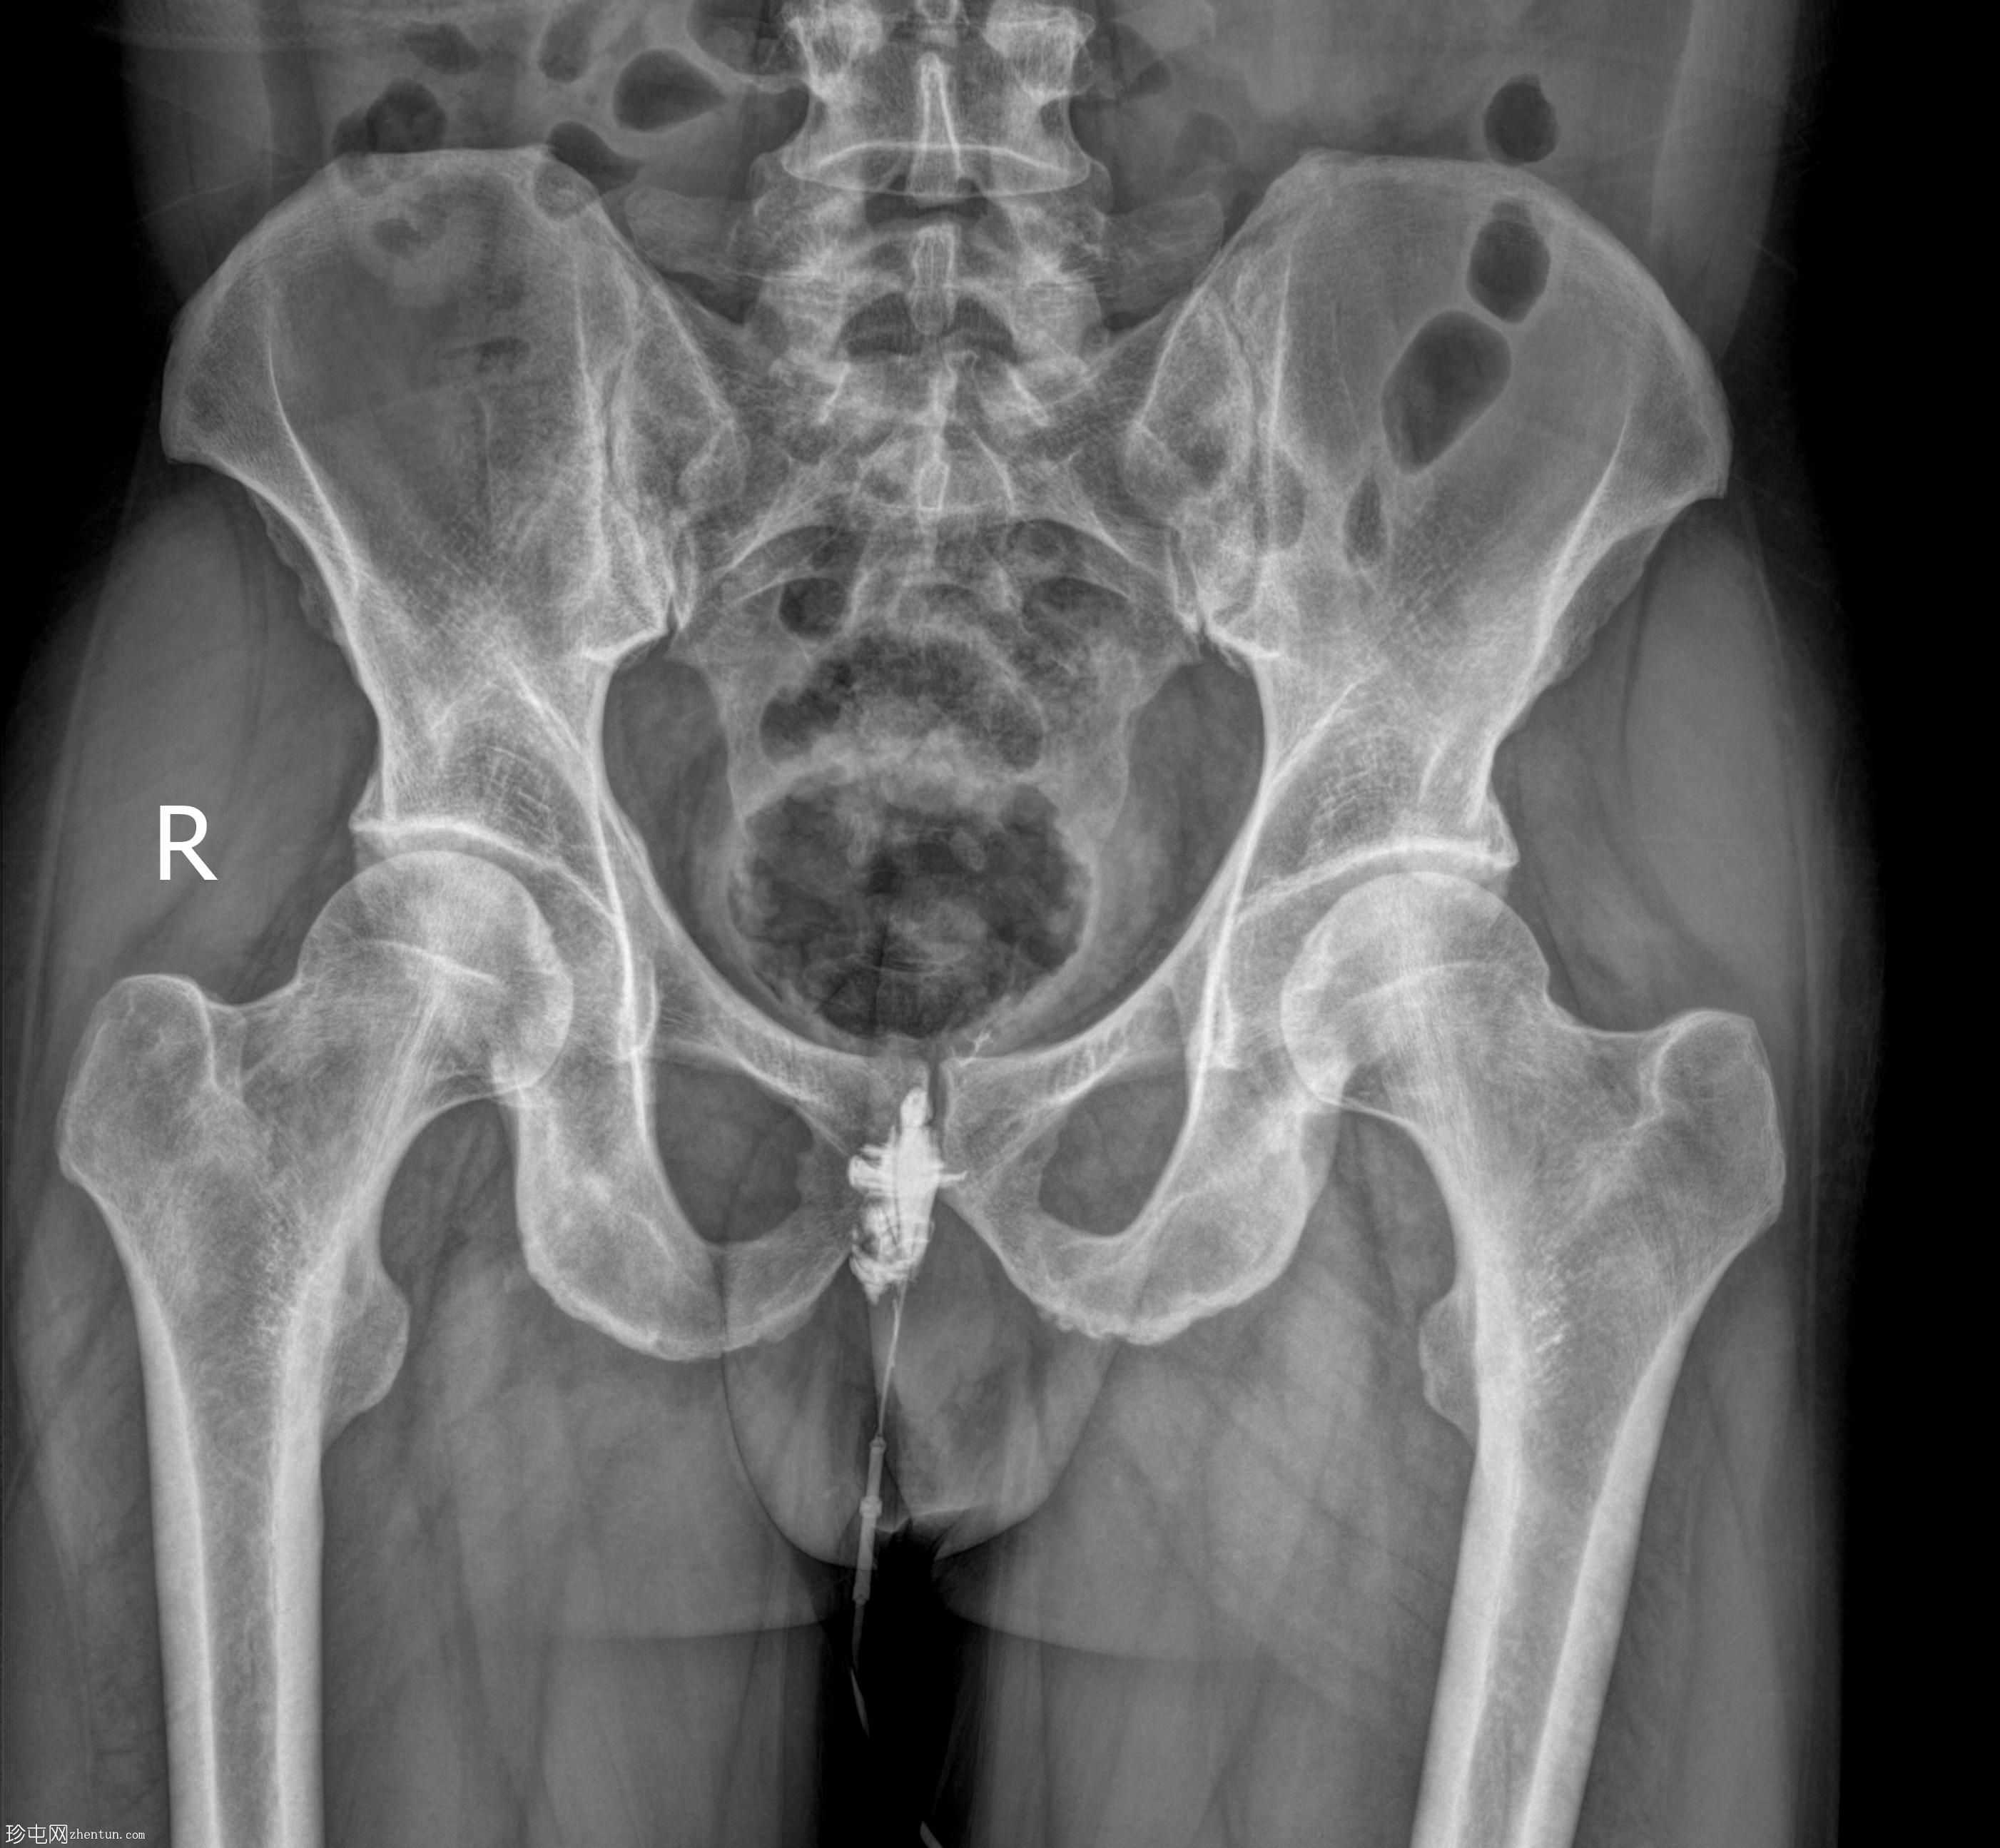

正位

经脓性分泌物开口注入造影剂,显示右侧肛周脓肿显影。

未见造影剂明显外渗至肛管或直肠。

透视瘘管造影图像显示右侧肛周脓肿较大,与肛管或直肠无交通。